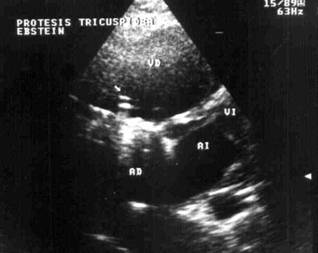

Figure 2: Trans-thoracic echocardiogram,

in the same tricuspid prosthesis where you can see that thrombus has

disappeared and normal functioning of the mechanical prosthesis 72 hours after

thrombolysis.

The symptoms disappeared and the TTE showed a total disappearance of the

thrombus and a recovery of the disc movements. There were no complications due

to the thrombolytic therapy.